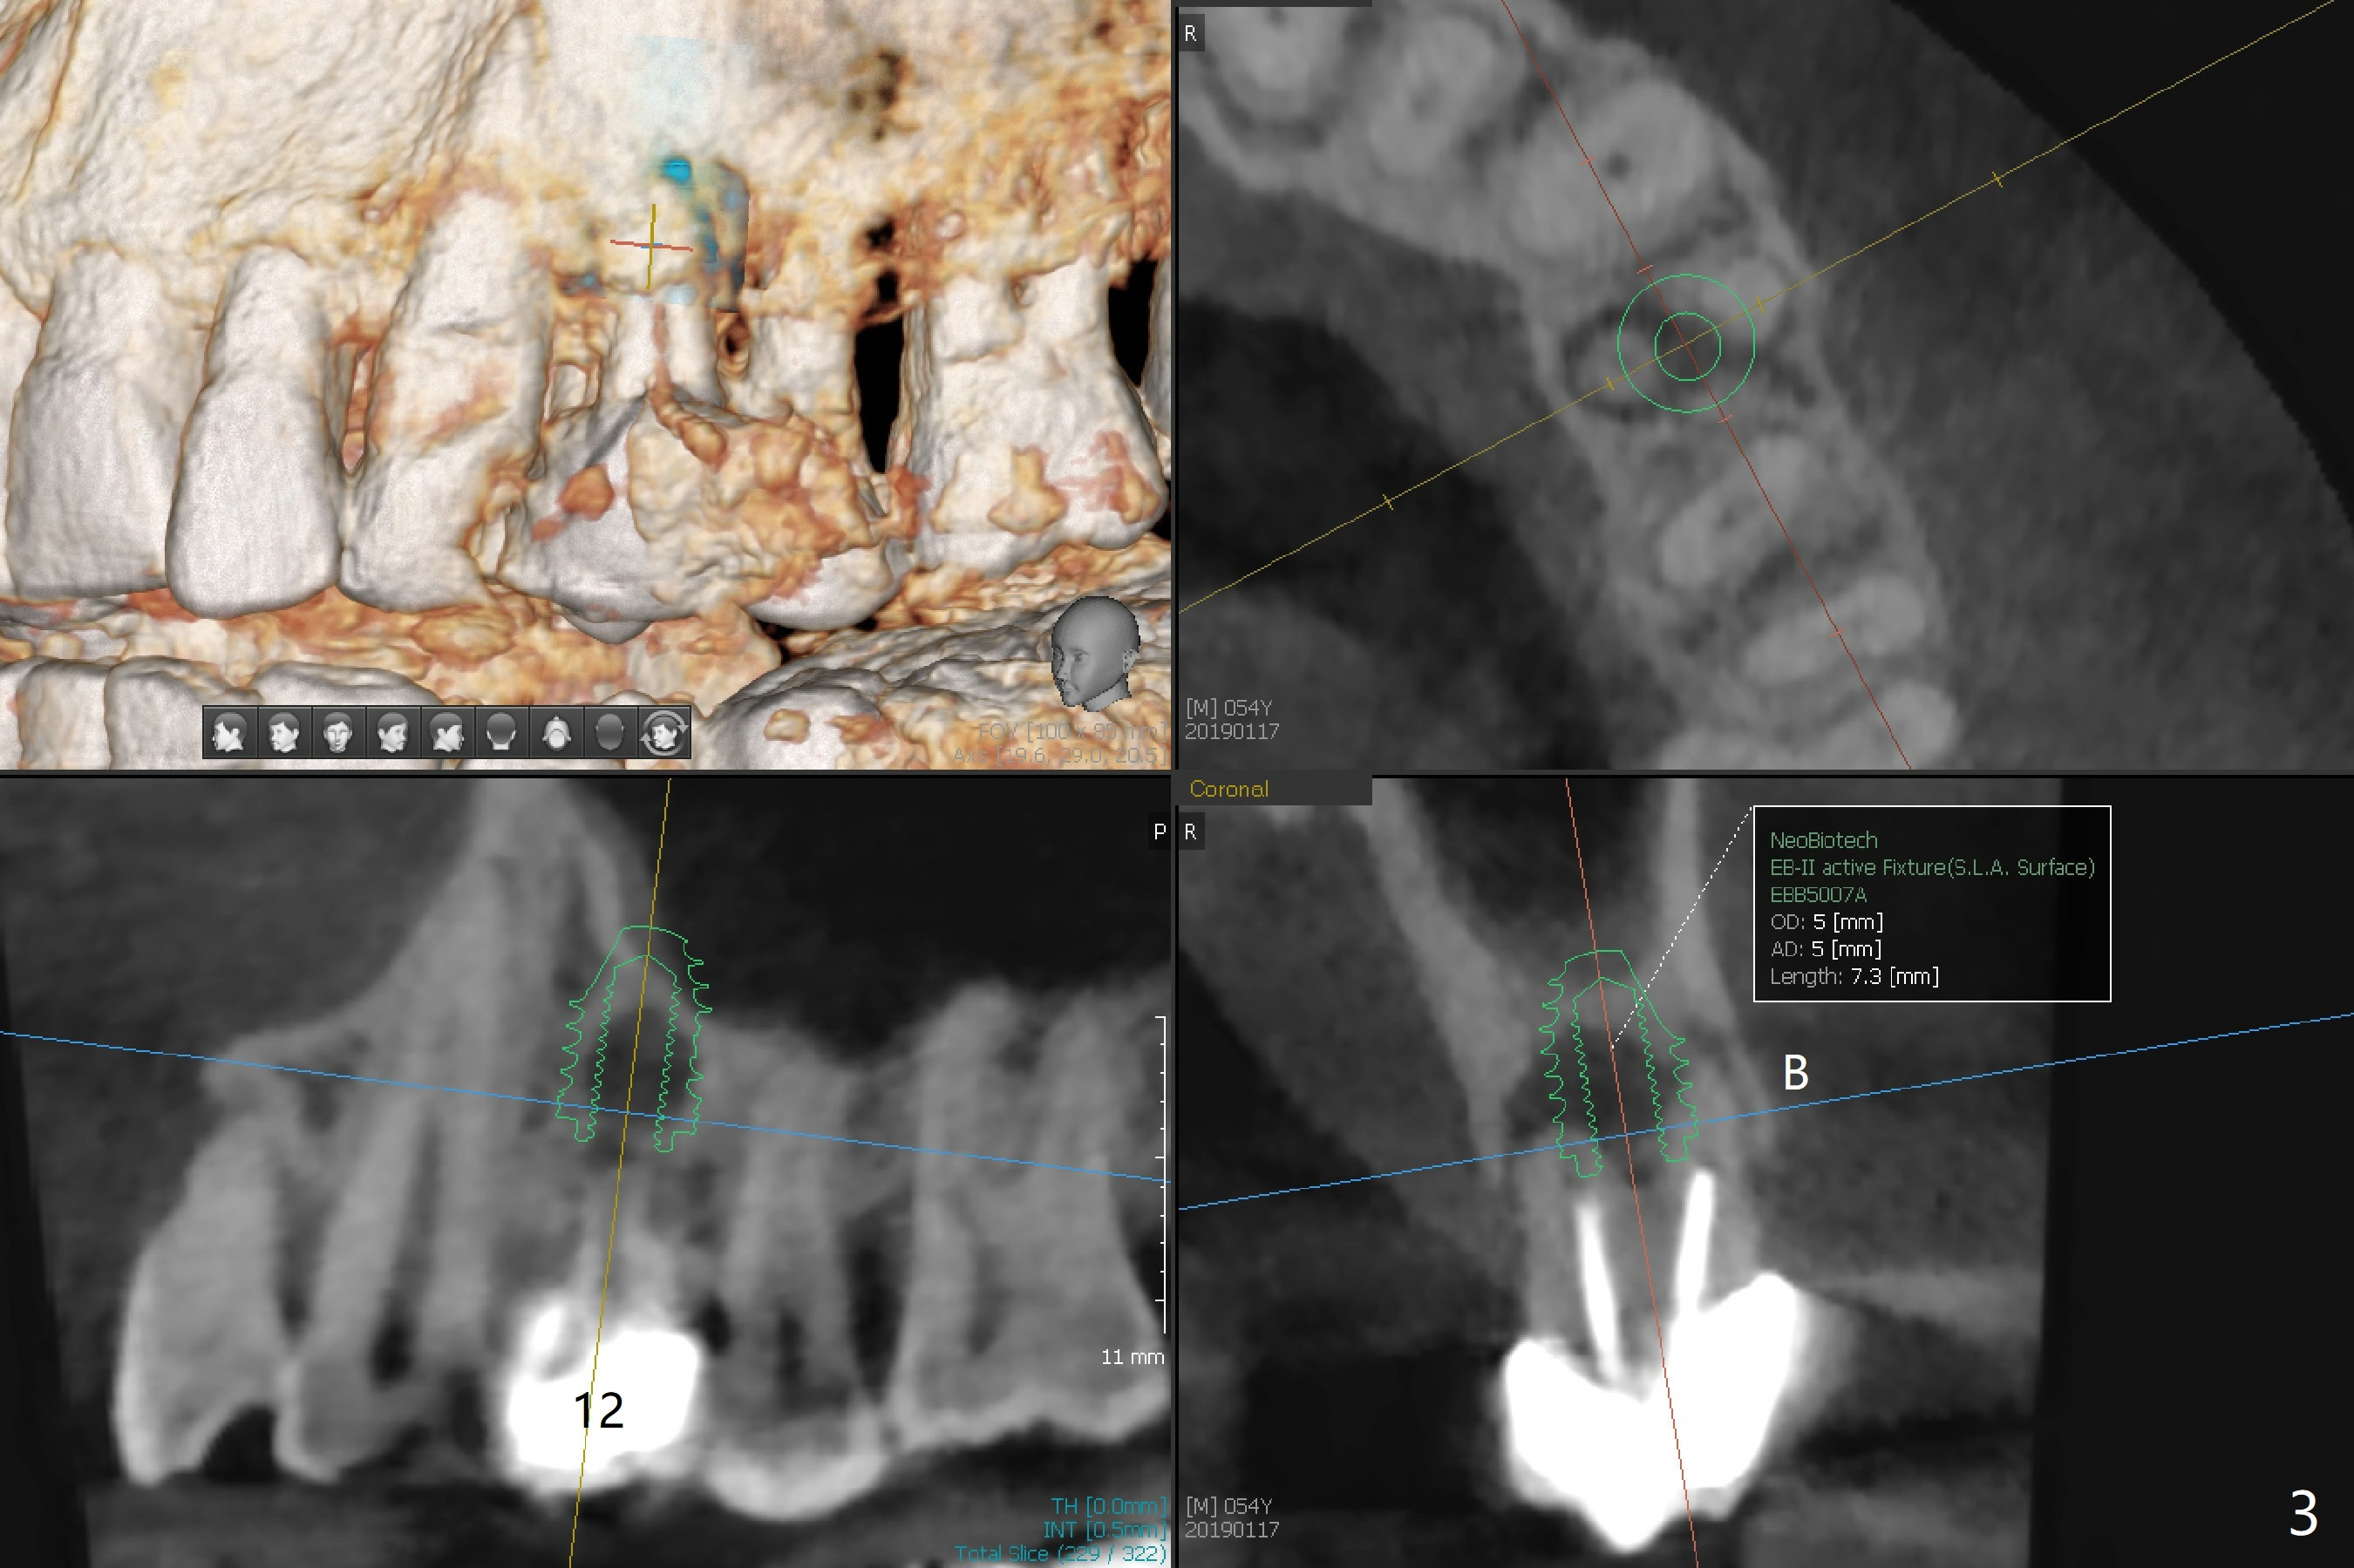

A 54-year-old man with bruxism requests treatment at #4 and 12 with buccal fistulae (Fig.1-3). Due to large defects, a large, but short implants (5x7.3 mm) will be used for primary stability. PRF membranes (x4) and liquid (x1 for sticky bone) will be prepared for sinus lift and buccal defect repair. Guided surgery will be utilized to prevent poor trajectory at #18 and 19 (Fig.1). The result turns out to be good (Fig.4).